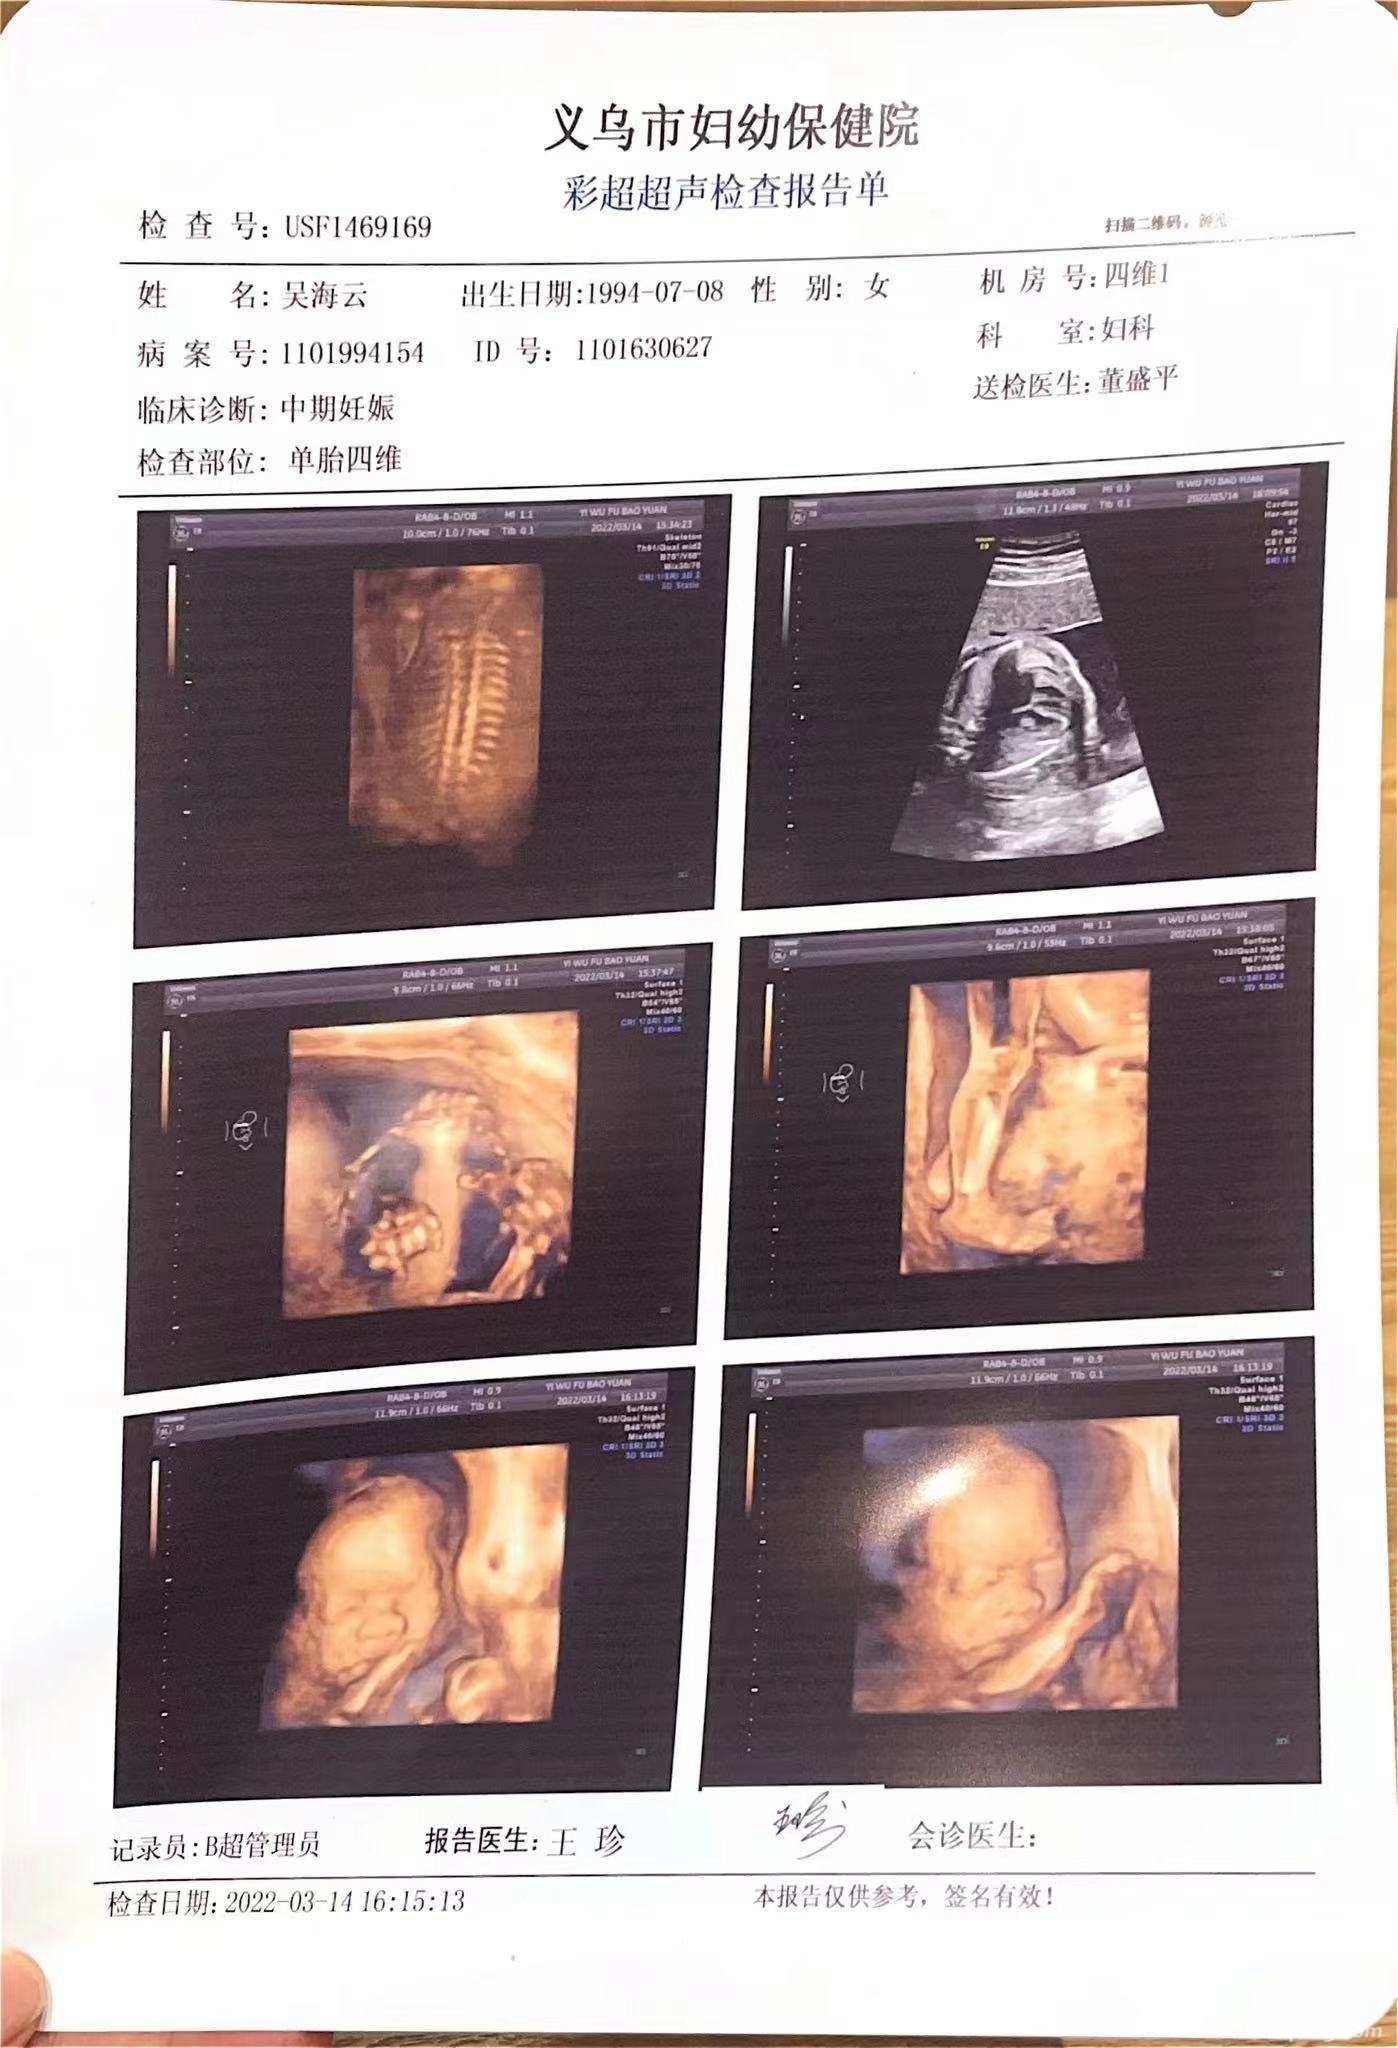

瞬间晴天霹雳,实在无法理解,老婆从怀孕到现在每次检查都是在妇幼保健院按照时间规定检查,每次的检查结果报告医生的答复都是“一切正常”,哪怕在出生前几个月的每次B超,彩超,等各项检查也是一切正常(有检查报告图片为证),而那时肚子里的孩子早已成型长大,如果有任何异常情况也应该是清晰可见。彩超所有的报告

俗话说,罗马不是一天建成的,碗大的肿瘤也不是几天就能长到这么大的,为什么直到出生前几天的各种产检,医生都看不出任何问题呢?我们带着所有的检查报告去了别的医院,也咨询了别的医生,在我们提供的一份日期是2022-3-14的彩超报告中,有另外的医生告诉我们,这份报告的图像里已经很明显可以看出婴儿背上有不明原因的深色阴影。而检查时的医生却仍说一切正常!B 超 彩超报告